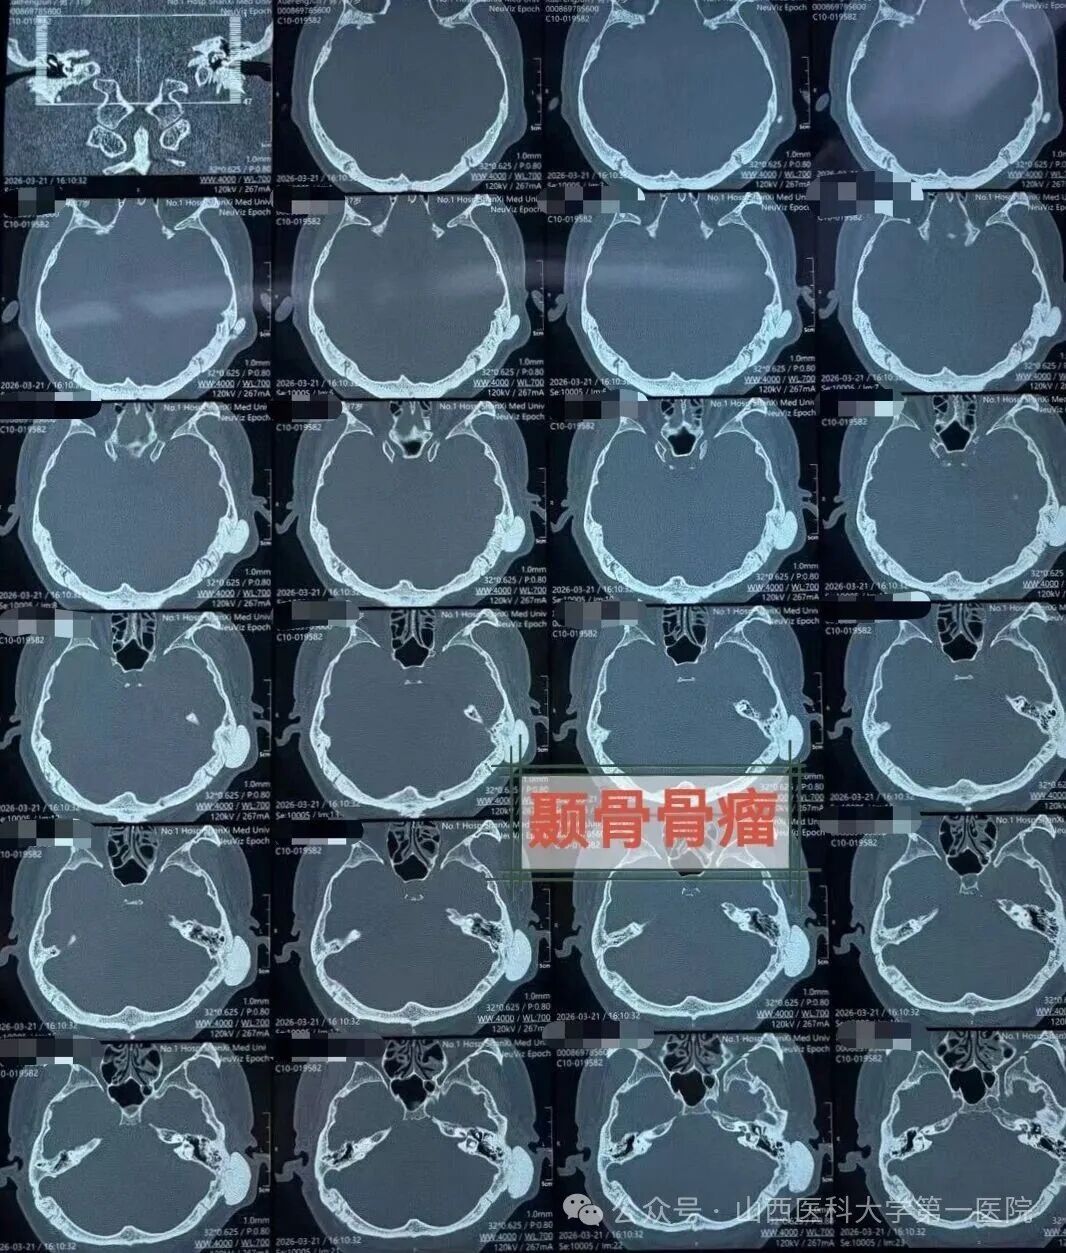

患者来自山西晋北,长期受间断性一侧偏头痛及头闷困扰,辗转求医无果,最终来到山医大一院耳鼻咽喉-头颈外科,经颞骨CT及头颅MRI检查,发现左侧颞骨鳞部有一约3.2cm×3.5cm×1.6cm的骨性肿瘤。肿瘤侵犯并破坏了颞骨鳞部、鼓部及乳突,波及颅中窝底,但未突入颅内,与静脉窦等重要神经血管关系密切。